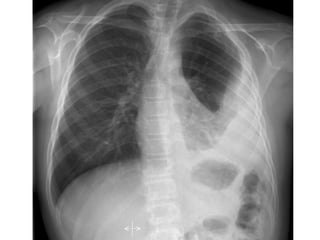

Rx tórax Niño: primoinfección. Patrón muy variable Adenopatías  hiliares ó mediastínicas: muy llamativas vs infiltrado Hiperinsuflación segmentaria y/o atelectasia (enfisema obstructivo <2 años)  Consolidación alveolar ó intersticial Derrame pleural  TBC miliar Adolescente: reactivación Cavitación Derrame pleural

Rx tórax Niño:primoinfección. Patrón muy variable Adenopatías hiliares ó mediastínicas: muy llamativas vs infiltrado Hiperinsuflación segmentaria y/o atelectasia (enfisema obstructivo <2 años) Consolidación alveolar ó intersticial Derrame pleural TBC miliar Adolescente: reactivación Cavitación Derrame pleural